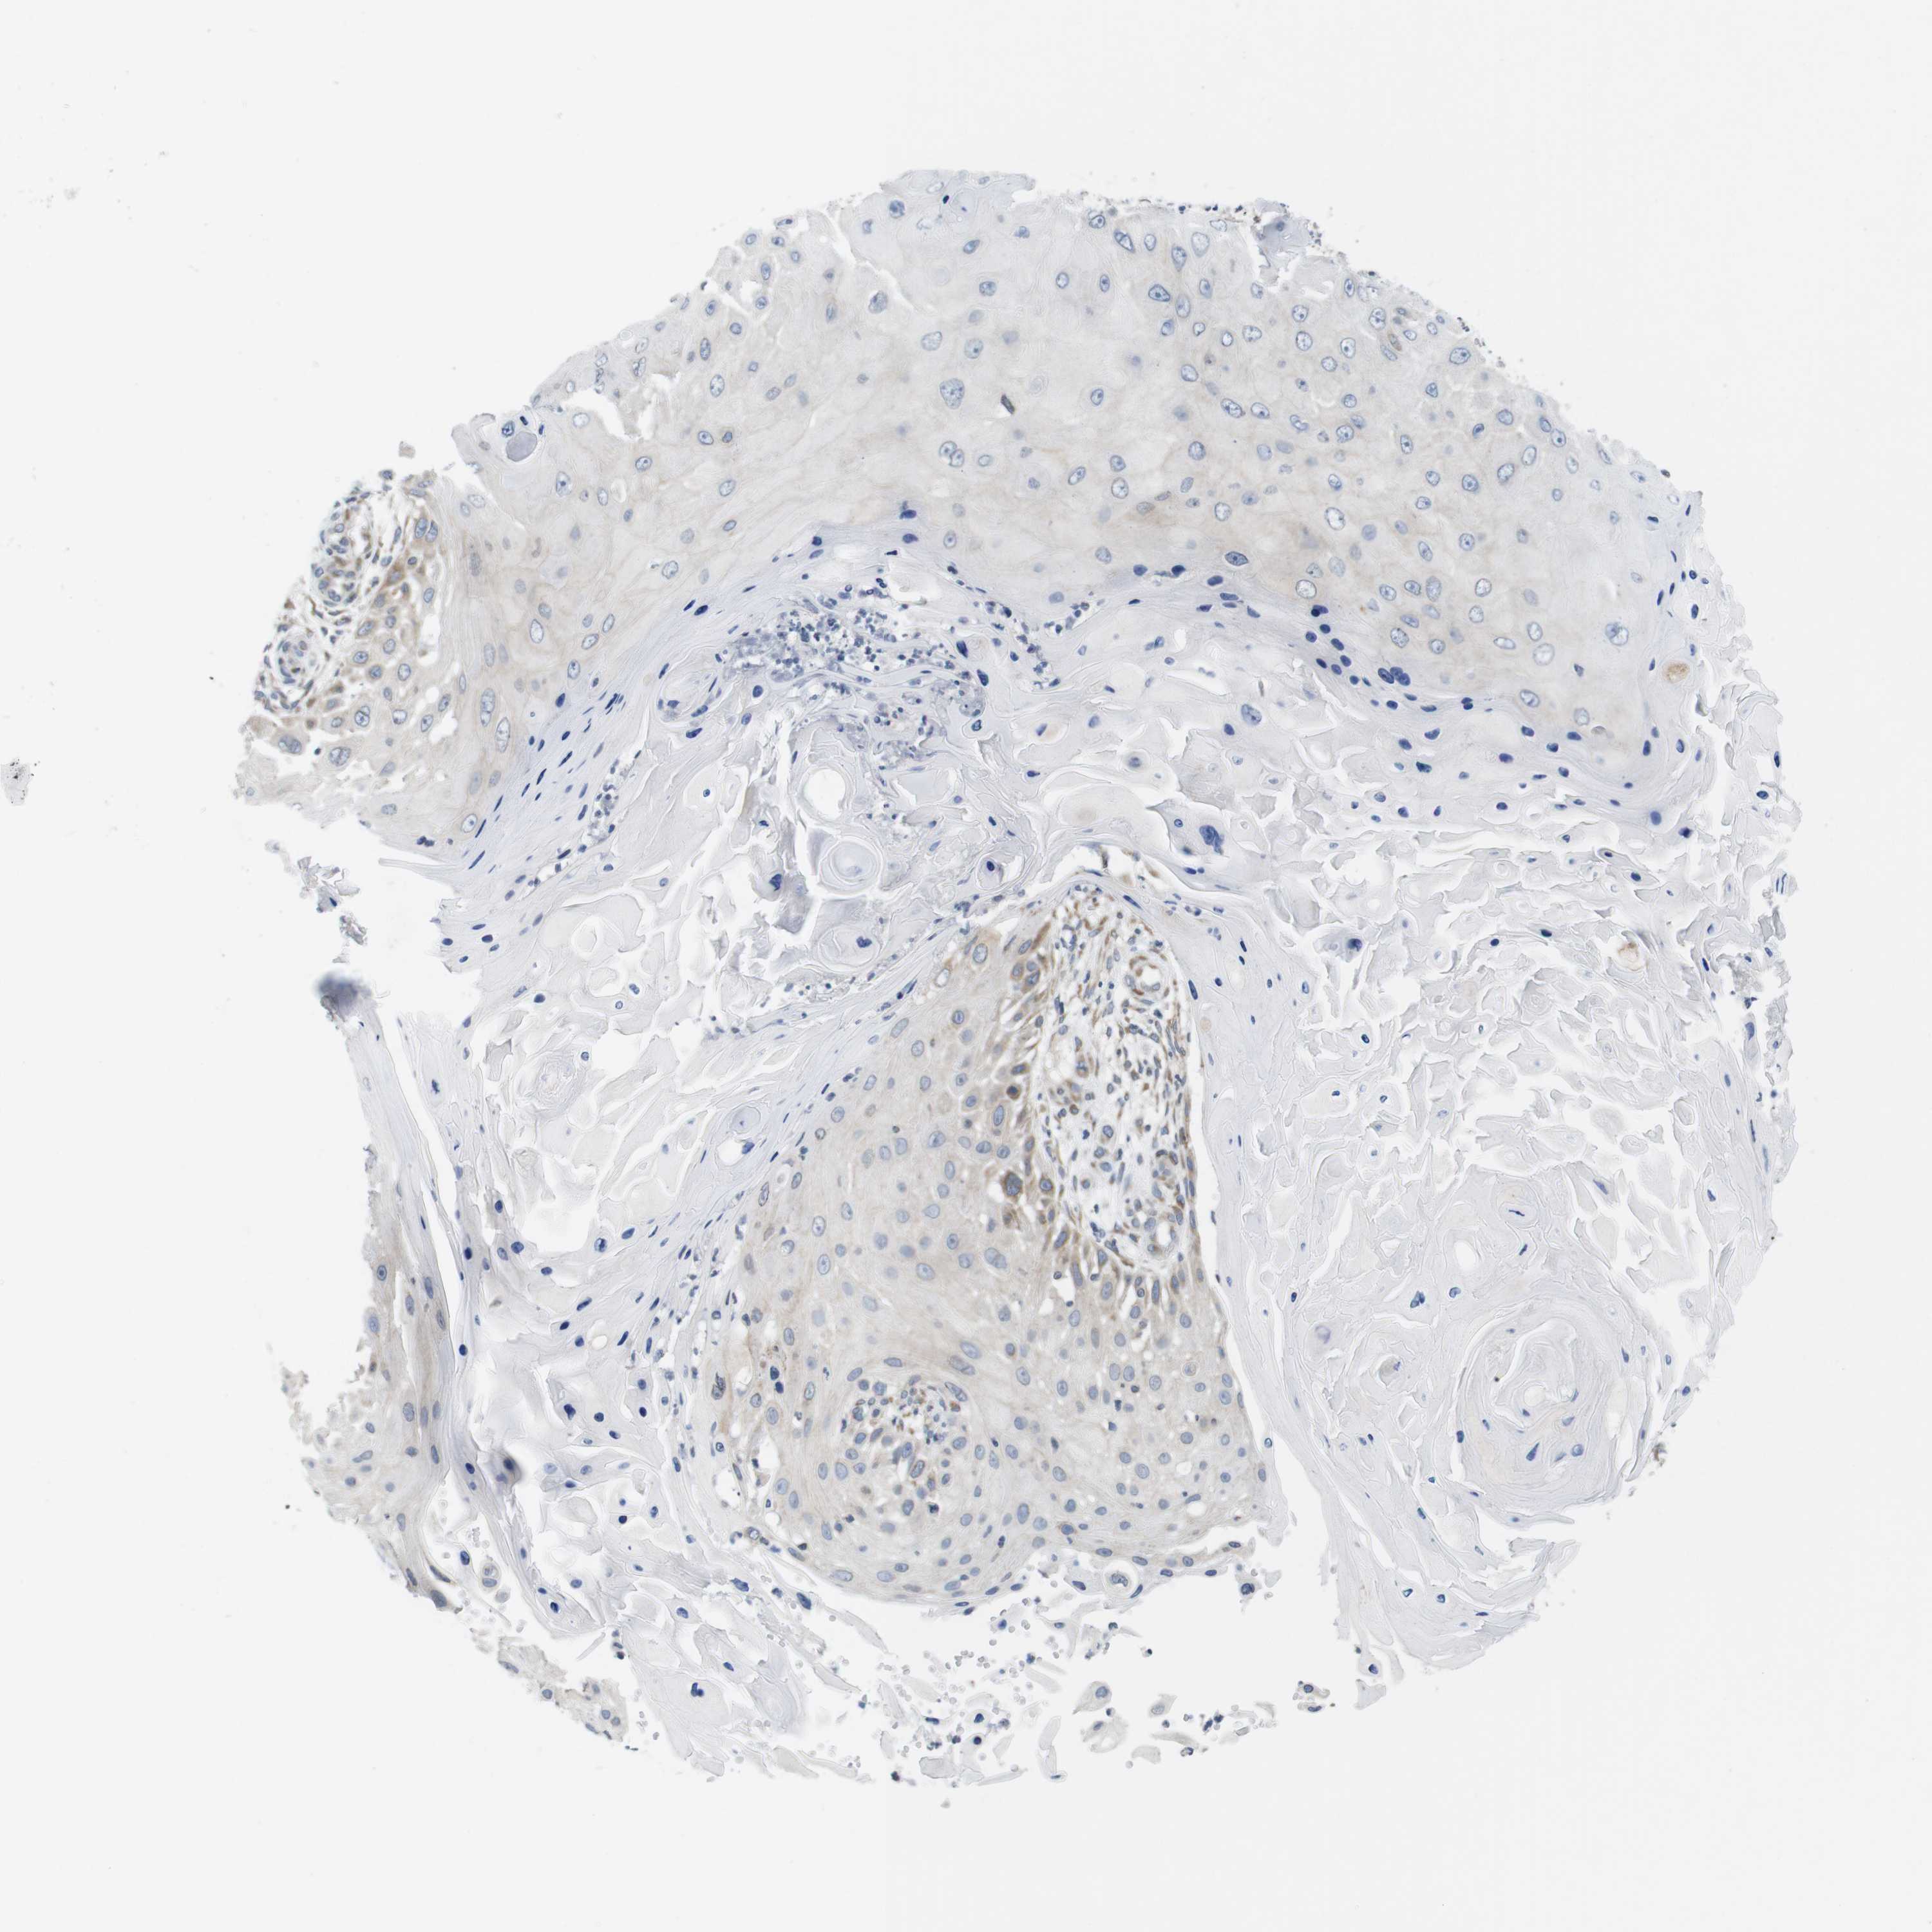

SKIN CANCER - Protein expressioni

A mouse-over function shows sample information and annotation data. Click on an image to view it in a full screen mode. Samples can be filtered based on level of antibody staining by selecting one or several of the following categories: high, medium, low and not detected. The assay and annotation is described here.

Each image is clickable and will lead to virtual microscopy that enables deeper exploration of all samples and also displays staining intensity scores, fraction scores and subcellular localization as well as patient and tissue information for each sample.

Antibody HPA015242

Squamous cell carcinoma, NOS